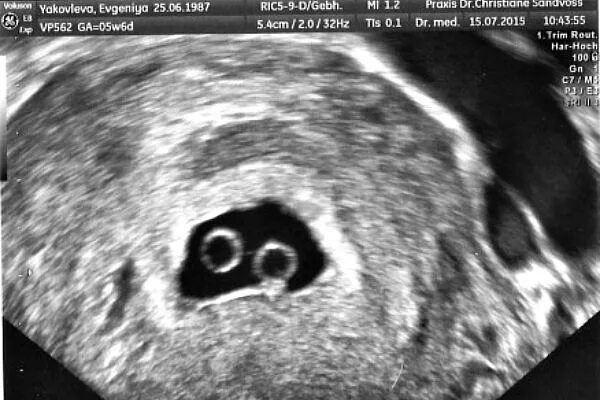

На каком сроке можно увидеть двойню